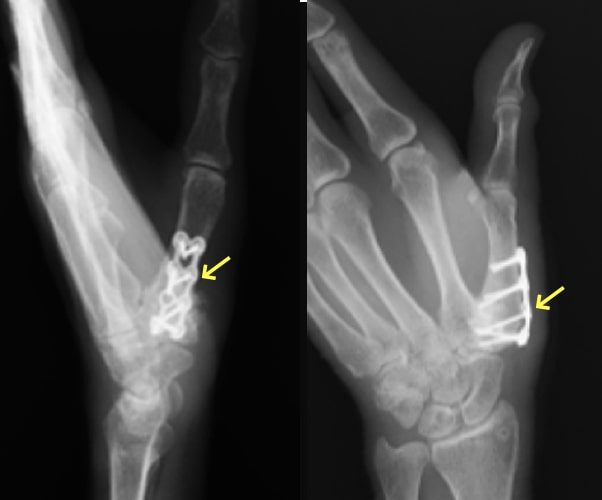

中手骨骨折 術前・術後写真

中手骨骨折術前・術後

指骨・中手骨骨折写真

基節骨変形癒合により指交差現象が出現

(握ると環指が小指に重なる)

原因

壁を殴ってしまったり、転倒した際に強打してしまったりして生じます。

症状

手や指が腫れて、痛くて動かせなくなります。変形を認める場合もあります。

治療方針

転位やズレの程度で治療方針を決めます。指の骨折の治療で重要なことは長期間固定をして拘縮を作らないことです。ほんの数週間の外固定により骨折部以外の関節も固くなってしまい、また少しの変形であっても指を握った時に重なったりする重篤な後遺症が生じることがありますので注意が必要です。手外科専門医にかかることをお勧めします。